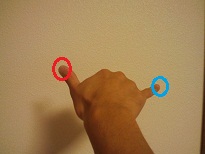

こんな感じ。すると、親指の爪を見ていると、小指が見えなくなっていると思います。この見えない範囲がマリオット盲点です。

どうでしょう?出来ました??